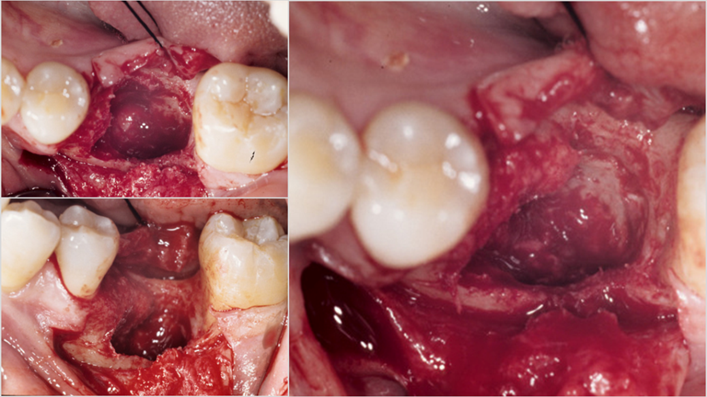

“AnyRidge implant enables fast and stable

osseointegration at this extreme case of bone defect. ”

Clinical case: Bone filling into the bottom of deepest thread at 8.0mm AnyRidge fixture

- Courtesy of Dr. Kwang Bum Park -

Keywords

AnyRidge, Knifethread ,extraction socket, ,initial stability ,Allograft, ,osseointegratio ,Dr. Kwang Bum Park, , Mandibular, Single replacement, AnyRidge, Mega-oss,

Products used

Implant system-AnyRidge, Regeneration-Mega-Oss